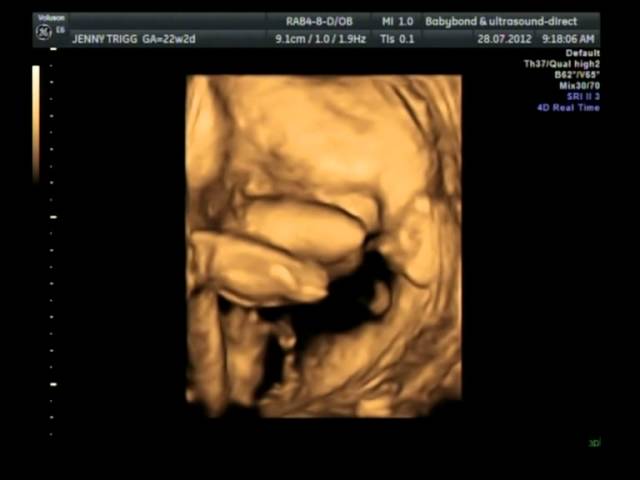

22 Week 3d Ultrasound. 22 weeks and 6 days. With the ultrasound imaging you would now get the first glimpse of your baby in photographs and videos. 5 Color Thermal 5 Black and White. Our 3D5D Ultrasound Image Gallery.

At 22 weeks pregnant an ultrasound will also reveal the sex of the baby although it is possible to inform the technician that you are not interested in knowing the sex of the baby as many parents do so. And since 3D and 4D ultrasound exams allow you to see your unborn baby in even more depth and detail than a standard 2D ultrasound you may be eager to book a photo op. 2nd Trimester Weeks 13-25. 3D4D Ultrasound Imaging HD Live Ultrasound 4D HD Live Ultrasound 2019-01-03T205412-0600 We went had this done and it was by far one of the most amazing things Ive ever done in my life. 14 Weeks Length. Our 3D5D Ultrasound Image Gallery.